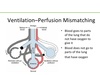

With COPD , ventilation and perfusion are _______ in lungs leading to chronic ______. Air flow is obstructed by thickening of bronchial walls due to edema or _____ _____. Excessive _______ mucus production. _____ of bronchial smooth muscle and interstitial fibrosis. It is most often reported in cats as ____ ____ and in mature ___-___ dogs.

mismatched

hypoxemia